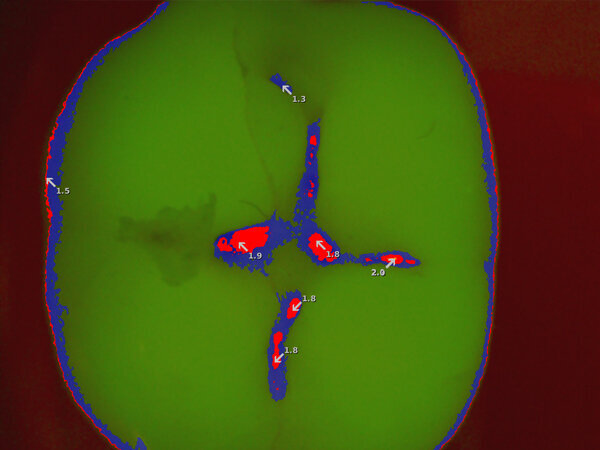

- Modalità di rilevamento della carie mediante l’impiego di specifiche lunghezze d’onda - È possibile mettere in risalto potenziali lesioni cariose che a occhio nudo potrebbero apparire dubbie.